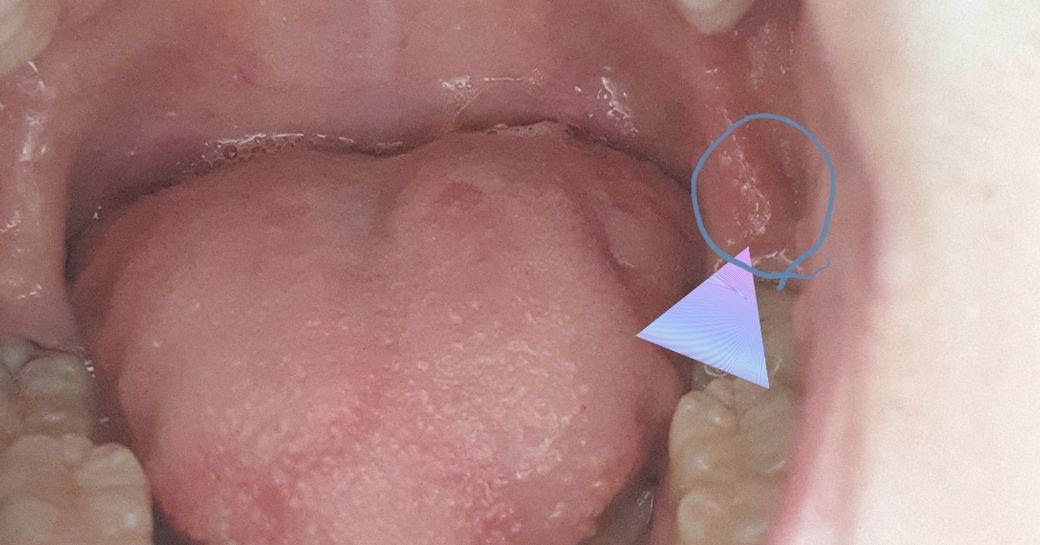

요새 프리랜서 일 때문에 2주 정도 계속 새벽 늦게 자다가 어제는 2~3시간 밖에 못 자서 일까 저녁에 보니 입 안쪽이 부었더라고요. 통증이 있거나 아프진 않고 잇몸이 아닌지라 크게 뭔가를 먹거나 마실때 불편하진 않습니다만. 푹 쉬고 회복 하면 나아질까요?

아마도 사랑니 뒷쪽 잇몸에 염증이 생긴 것으로 보입니다.

컨디션 좋아지면 저절로 가라앉기도 하지만 안 가라앉으면 항생제 복용하고 치과에서 치료해야 합니다.

해당 부위에 표시한 자료로 인하여 정확히 판단하기 힘듭니다. 잇몸이 부운 원인을 찾기 위해서는 방사선 사진 및 임상 검사를 해보아야할 것으로 보입니다. 만약에 단순히 구강 내 외상(trauma)이거나 구내염이라면 2주 안에 회복될 것으로 보이나 사랑니나 아래 위 교합이 불균형해서 나타났다면 해당 원인을 제거해야할 것으로 보입니다.

해당 부위는 약간 부은 듯이 보일 수 있습니다.

또한 위의 사랑니가 내려왔다면 해당 부위의 잇몸을 자극하기 때문에 붓거나 할수 있어요.

이런 경우에는 잇몸을 자극하는 부위를 다듬어 줄 수 있습니다.